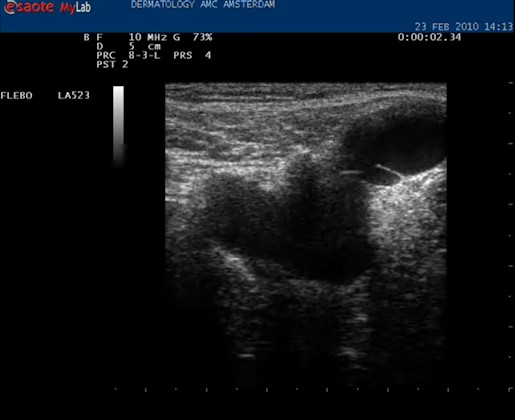

| Daarna de echokop draaien in de lengte richting van het vat. Nu is het mooi helemaal in beeld. |

| Video: vena saphena magna op de normale diepte, liggend tussen twee fasciebladen. De VSM wordt eerst opgezocht, in het midden geplaatst en dan wordt de echokop in de lengte richting gedraaid. |

| Het is mogelijk om de diameter op te meten van het vat. Het kan handig zijn om dat te weten in verband met de therapie; of er bijvoorbeeld een VNUS catheter doorheen kan. |